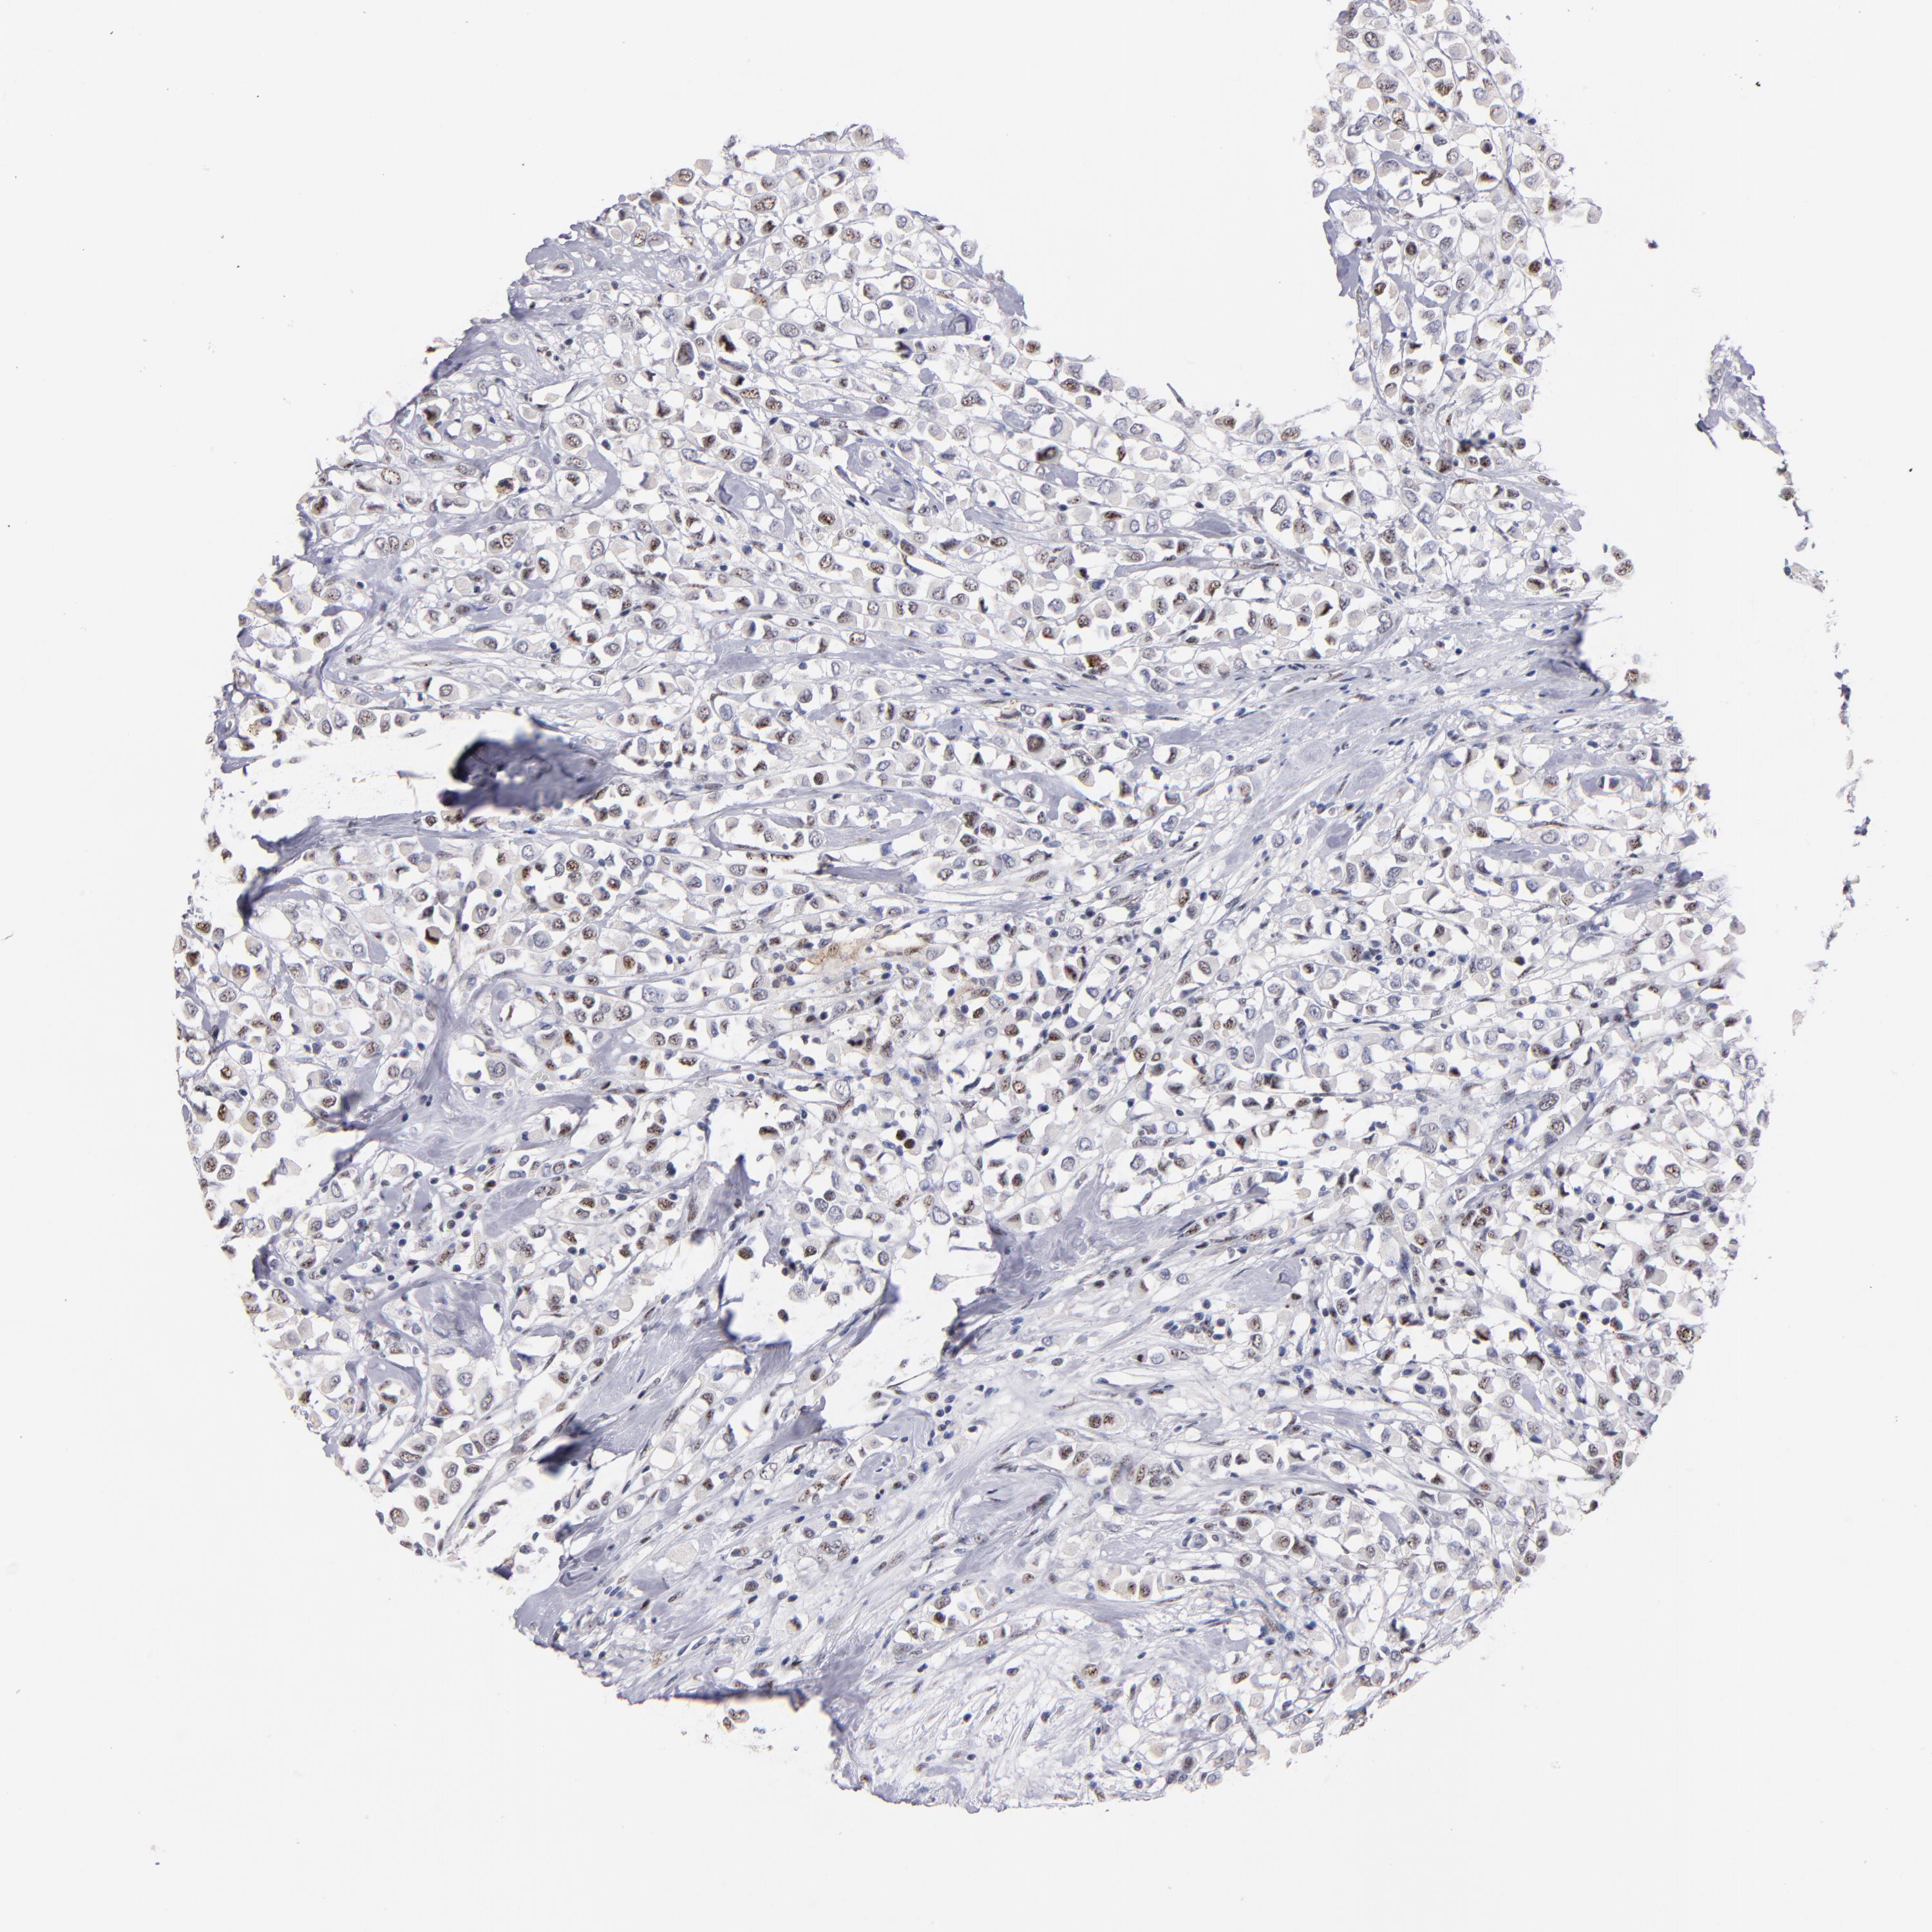

BRCA TCGA BRCA VALIDATION PROTEIN EXPRESSION